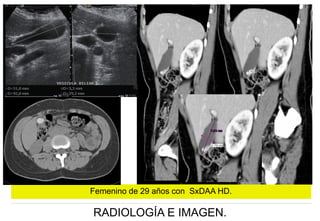

Femenino de 29 años con SxDAA HD.